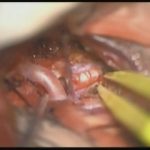

術中写真

摘出 前